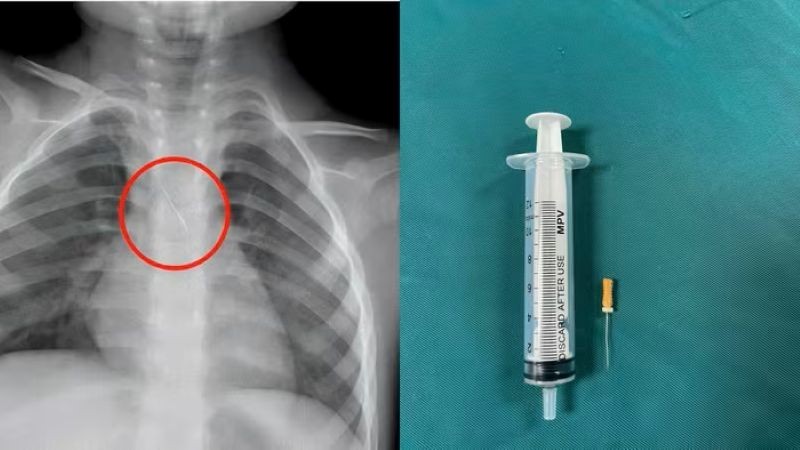

Quảng Trị: Kịp thời cứu cháu bé bị kim chọc tủy rơi vào đường thở

Chủ Nhật, ngày 16/11/2025 08:23Ngày 15/11, Bệnh viện Đa khoa tỉnh Quảng Trị cho biết vừa cấp cứu thành công một cháu bé 3 tuổi bị kim chọc tủy dài 22mm rơi vào đường thở. Dị vật trong đường thở của bệnh...